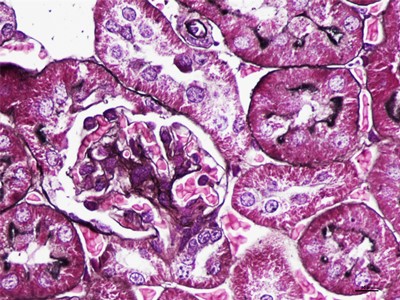

HE染色简称苏木精是是一种由碱性染液苏木精和酸性染液伊红构成的一种染色方法。是通显微镜下观察病理切片里病变的组织学形态变化来诊断疾病的,适用于胚胎学、病理学,生物医学,病理学教学与科研。HE染色对碱性染料和酸性染料亲和力都比较弱的现象称为中性。组织切片苏木素染色、分化与反蓝:将水化后的组织样本的切片使用PBS溶液浸泡清洗,每次浸泡5min,总共清洗3次。之后用移液枪吸取已经预先配置好的苏木素染色液,每个组织切片滴加100ul,充分染色10min。切片经HE染色后,要彻底脱水透明,才能用重庆中性树胶封盖。he染色对于贴壁生长细胞,胰酶消化,调整细胞浓度约1×105/ml,滴加于盖玻片上(置于6孔板中),培养相应时间后,取出细胞爬片,用PBS 洗涤3次。着色情况与组织或细胞的种类有关。切片在苏木素染液中停留过长;或切片太厚;或分化时间太短。这种情况首先镜下看看切片厚度(最佳厚度1-2层细胞核),要么重新染色,要么重新制片。染色的最终结果是:细胞核呈蓝色、胞质、肌纤维、胶原纤维和红细胞呈深浅不一样的红色,病理技术服务提醒:在进行HE染色需要染色时间,脱水,染色时间不一样,需要等 ,明确HE评判标准。